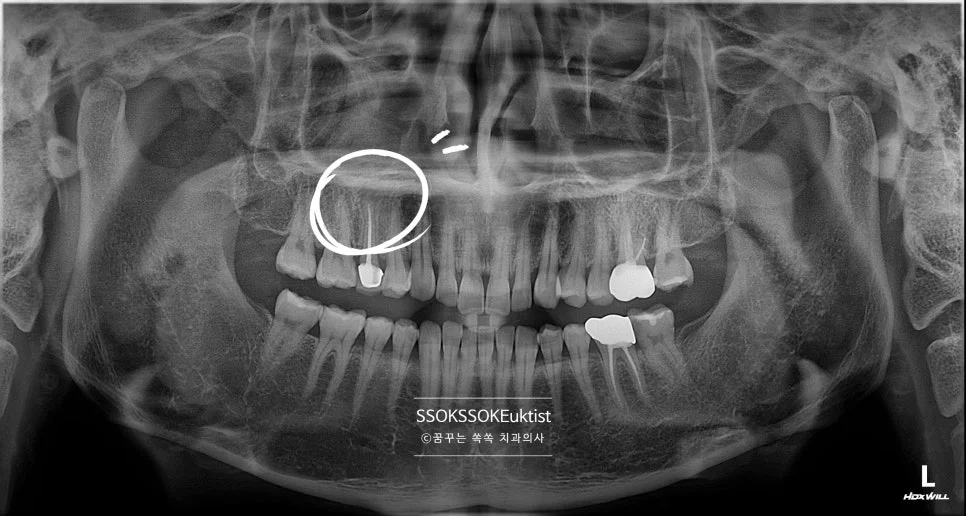

신경치료 케이스1 초진 파노라마 엑스레이

좋은 진료를 정직하게 | 선한 영향력으로 더 나은 가치를 신경치료 통증 없이 받으려면? 치수염 진단부터 크라운까지 전 과정 꿈꾸는 쏙쏙 치과의사 박상억입니다 오늘은 치과 치료의 화룡정점이라고 할 수 있는 치아의 신경치료에 대해 설명드릴까 합니다. 신경 치료는 그 이름부터 무시무시한데 실제 통증과 감각을 느끼는 신경 그 자체를 다루는 치료다 보니 엄청난 통증이 있는 상태에서 아주 편안한 … 더 읽기